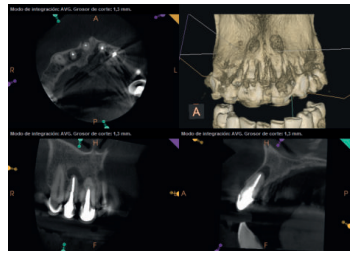

Para confirmar el origen endodóntico y el tamaño de las lesiones se realizaron exploraciones tomográficas con espesor de corte de 75 micras mediante CBCT CS8100 (Carestream Dental® ) en las que se evidenciaron lesiones periapicales radiolúcidas a nivel de 12, 11, 21 (con afectación bicortical), 25 y raíces vestibulares de 26 (Figuras 4 a 8).

A los seis meses el paciente acudió a revisión sin ninguna sintomatología, tanto a nivel anterior como posterior. En las radiografías periapicales se apreció una disminución en el tamaño de las lesiones periapicales radiolúcidas preexistentes (Figuras 10 y 11). Dado que faltaba tratar la lesión del 25, se realizó CBCT de control donde se comprobó la mejoría a nivel del 26 (Figura 12), por lo que se programó la microcirugía del 25.

Una vez realizada la microcirugía del 25, el paciente no volvió a presentar ninguna sintomatología y las tomografías de control a 12 meses (en 25) y a 18 meses en los dientes restantes mostraron la regeneración de las lesiones periapicales radiolúcidas preexistentes en todos los dientes tratados (Figuras 13 a 16).

Se realizaron controles radiológicos a los 6, 12 y 18 meses mediante CBCT, apreciándose ausencia de sintomatología y reversión del cuadro infeccioso crónico, así como progresividad y estabilidad en la regeneración ósea apical. A nivel del 21 se aprecia radioopacidad periapical, sin pérdida de volumen, y ausencia de invasión del espacio preservado por el tejido blando circundante. Si bien algunos autores han utilizado plasma rico en factores de crecimiento (PRGF) asociado a Bio-Oss® y Bio-Gide® en casos similares al nuestro, hemos obtenido un resultado adecuado sin aplicar PRGF como técnica complementaria13.